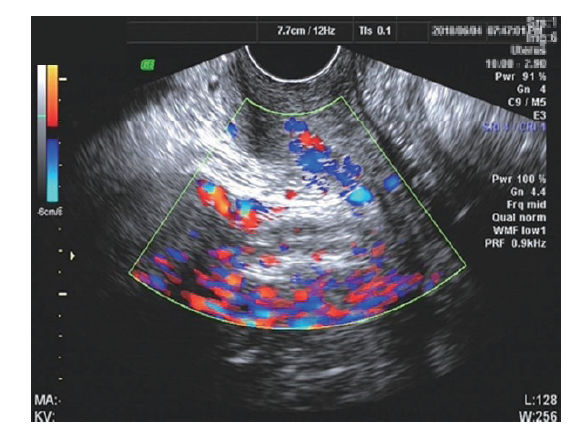

初步诊断:卵巢卵黄囊瘤可能。2018年6月6日行剖腹探查,术中见盆腔巨大包块(图2A)与乙状结肠、直肠、子宫后壁及右侧卵巢粘连,分离粘连后见子宫双侧附件外观正常,子宫直肠陷凹封闭,包块来源于后腹膜,予经腹盆腔巨大肿物切除术、小肠部分切除术、盆腔粘连松解术。术后病理结果提示镜下见异形细胞呈腺样、条索状或迷路样排列,可见Schiller-Duval(S-D)小体,腺样结构内的被覆上皮部分肥胖,部分扁平,核分裂易见,间质疏松、黏液样变性明显,并见嗜酸性小体。免疫组织化学染色:角蛋白(CK,+),胎盘碱性磷酸酶(PLAP,+),甲胎蛋白(+),HCG(-),CD30(-),Oct3/4(-),上皮膜抗原(EMA,-),抑制素(inhibin,-),波形蛋白(Vim,-),细胞增殖抗原Ki67(40%+),Gly-3(部分+),见图2B。考虑卵黄囊瘤。术后予依托泊苷150 mg、卡铂900 mg、博来霉素15 mg(BEP方案)静脉化学治疗,共化学治疗6次。第3次化学治疗后(2018年8月6日)复查甲胎蛋白降至正常(图2C),彩超未见明显异常肿物。随访1年至撰稿日未见肿瘤复发。

图2 一例后腹膜卵黄囊瘤患者的术中切除肿物、病理结果以及手术前后血清甲胎蛋白水平

A:术中切除后腹膜肿物大体标本;B:后腹膜肿物HE染色(×400);C:患者术前及术后血清甲胎蛋白水平变化